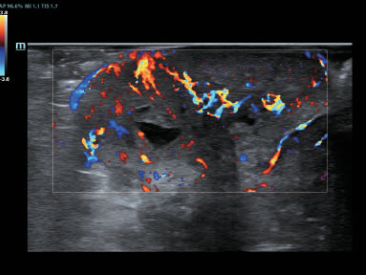

–€–Ψ–Ϋ–Ψ–Κ―Ä–Η―¹―²–Α–Μ–Μ–Η―΅–Β―¹–Κ–Η–Β –¥–Α―²―΅–Η–Κ–Η ―¹ ―²–Β―Ö–Ϋ–Ψ–Μ–Ψ–≥–Η–Β–Ι 3–Δ?

–ë–Μ–Α–≥–Ψ–¥–Α―Ä―è ―¹–Ψ―΅–Β―²–Α–Ϋ–Η―é ―²–Β―Ö–Ϋ–Ψ–Μ–Ψ–≥–Η–Η 3–Δ? (–Δ―Ä–Ψ–Ι–Ϋ–Ψ–Ι ―¹–Ψ–≥–Μ–Α―¹―É―é―â–Η–Ι ―¹–Μ–Ψ–Ι, ―²–Β―Ö–Ϋ–Ψ–Μ–Ψ–≥–Η―è –Ω–Ψ–Μ–Ϋ–Ψ―¹―²―¨―é ―Ä–Α–Ζ–¥–Β–Μ–Β–Ϋ–Ϋ―΄―Ö –Κ―Ä–Η―¹―²–Α–Μ–Μ–Ψ–≤, ―²–Β―Ä–Φ–Ψ–Κ–Ψ–Ϋ―²―Ä–Ψ–Μ―¨ –Α–Κ―É―¹―²–Η―΅–Β―¹–Κ–Ψ–Ι –Μ–Η–Ϋ–Ζ―΄) –Η –Φ–Ψ–Ϋ–Ψ–Κ―Ä–Η―¹―²–Α–Μ–Μ–Η―΅–Β―¹–Κ–Η―Ö –¥–Α―²―΅–Η–Κ–Ψ–≤ –Ψ–±–Β―¹–Ω–Β―΅–Η–≤–Α–Β―²―¹―è –Κ–Α–Κ –±–Ψ–Μ–Β–Β –≤―΄―¹–Ψ–Κ–Α―è ―Ä–Α–Ζ―Ä–Β―à–Α―é―â–Α―è, ―²–Α–Κ –Η –Ω―Ä–Ψ–Ϋ–Η–Κ–Α―é―â–Α―è ―¹–Ω–Ψ―¹–Ψ–±–Ϋ–Ψ―¹―²―¨, –≤ ―Ä–Β–Ζ―É–Μ―¨―²–Α―²–Β ―΅–Β–≥–Ψ ―Ä–Β―à–Α–Β―²―¹―è –Ω―Ä–Ψ–±–Μ–Β–Φ–Α –Η―¹―¹–Μ–Β–¥–Ψ–≤–Α–Ϋ–Η–Ι ―²–Β―Ö–Ϋ–Η―΅–Β―¹–Κ–Η ―¹–Μ–Ψ–Ε–Ϋ―΄―Ö –Ω–Α―Ü–Η–Β–Ϋ―²–Ψ–≤.